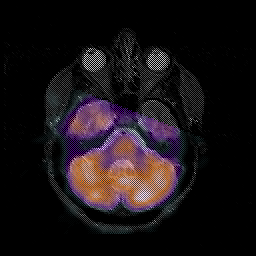

Glioblastoma multiforme overlay -- Slice #16

[Home][Help][Clinical][Tour 1][Tour 2][Tour 3] Slice 16